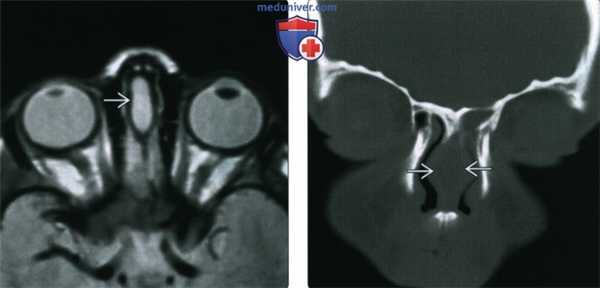

(Слева) При аксиальной МРТ PD FSE определяются типичные признаки синусного тракта носа в носовой перегородке (от основания черепа до кончика носа).

(Справа) При корональной КТ в костном окне в носовой перегородке визуализируется типичная гиоденсная дермоидная киста.